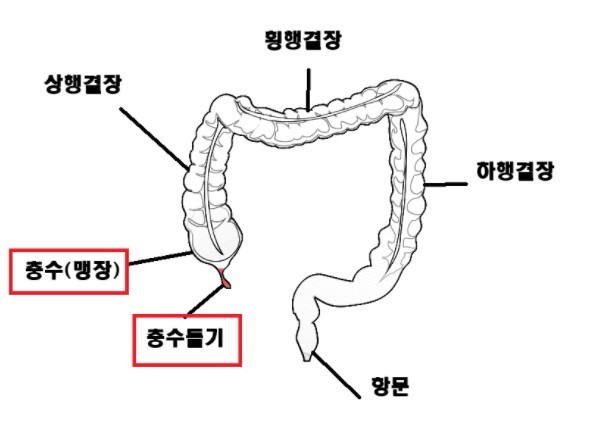

맹장? 충수돌기? 맹장염이 뭐에요??

맹장염(충수돌기염)은 대장의 시작점 옆에 붙은 가는 주머니(충수돌기)에 염증이 생기는 질환이죠.

대장이 시작되는 부위를 “막힌 장”이라고 해서 맹장, 한자로는 “충수”라고 불러서 편하게 “맹장염”, “충수염”이라고 많이들 부르지만 정확한 용어는 “충수”의 밑에 붙어있는 돌기에 염증이 발생하는 “충수돌기염”입니다.

이 “충수돌기”는 좁고 가느다란 돼지꼬리처럼 생긴 장기라서,입구가 막히면 내부 압력과 세균 증식으로 곪고, 진행하면 터져서 천공·복막염까지 이어질 수 있습니다.